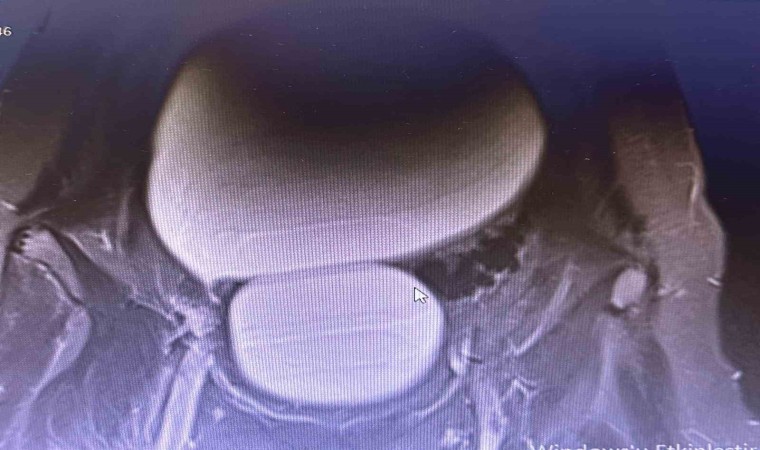

Sivas’ta yaşayan 12 yaşındaki N.B. şiddetli karın ağrıları ve düzensiz adet kanamaları şikayetiyle hastaneye başvurdu. Yapılan detaylı tetkikler sonucunda genç kızın karın bölgesinde yaklaşık 25 santimetre çapında adeta kavun büyüklüğünde bir kist olduğu tespit edildi. Medicana Sivas Hastanesi’nde Çocuk Cerrahisi Uzmanı Op. Dr. Mahmut Aluç tarafından gerçekleştirilen başarılı bir operasyonla, genç kızın sol yumurtalığında bulunan ve karaciğere kadar uzanan devasa kist içerisindeki 1.6 litre su boşaltılıp, başarıyla çıkarıldı. Sağlığına kavuşan genç kız taburcu edildi.

Çocuk Cerrahisi Uzmanı Op. Dr. Mahmut Aluç, kisttin içerisinden yaklaşık 1.6 litre sıvı boşaltıldığını söyleyerek, “ Karın ağrısı, düzensiz adet şikayetiyle bize geldi. Dışarıda yapan tetkiklerde ve bizde yapılan tetkiklerinde karın içerisinde yaklaşık yirmi beş santimetrelik çapında bir kitli kitle tespit ettik. Burada da tetkiklerimize tekrar baktığımızda sol över kökenli bir kisttik yapı olduğunun farkına vardık. Gerekli incelemeleri yaptıktan sonra ve ailenin onayını aldıktan sonra hastayı operasyona aldık. Karaciğere kadar uzanan bir kisttik yapımız vardı. Onun içerisinde yaklaşık 1.6 litre sıvı boşalttık. Over dokusunu, yumurtalık dokusunu koruyarak kisti tamamen eksize ettik. Hastamızı şifayla taburcu ettik. Patoloji sonucumuz da iyi huylu olarak geldi” dedi.